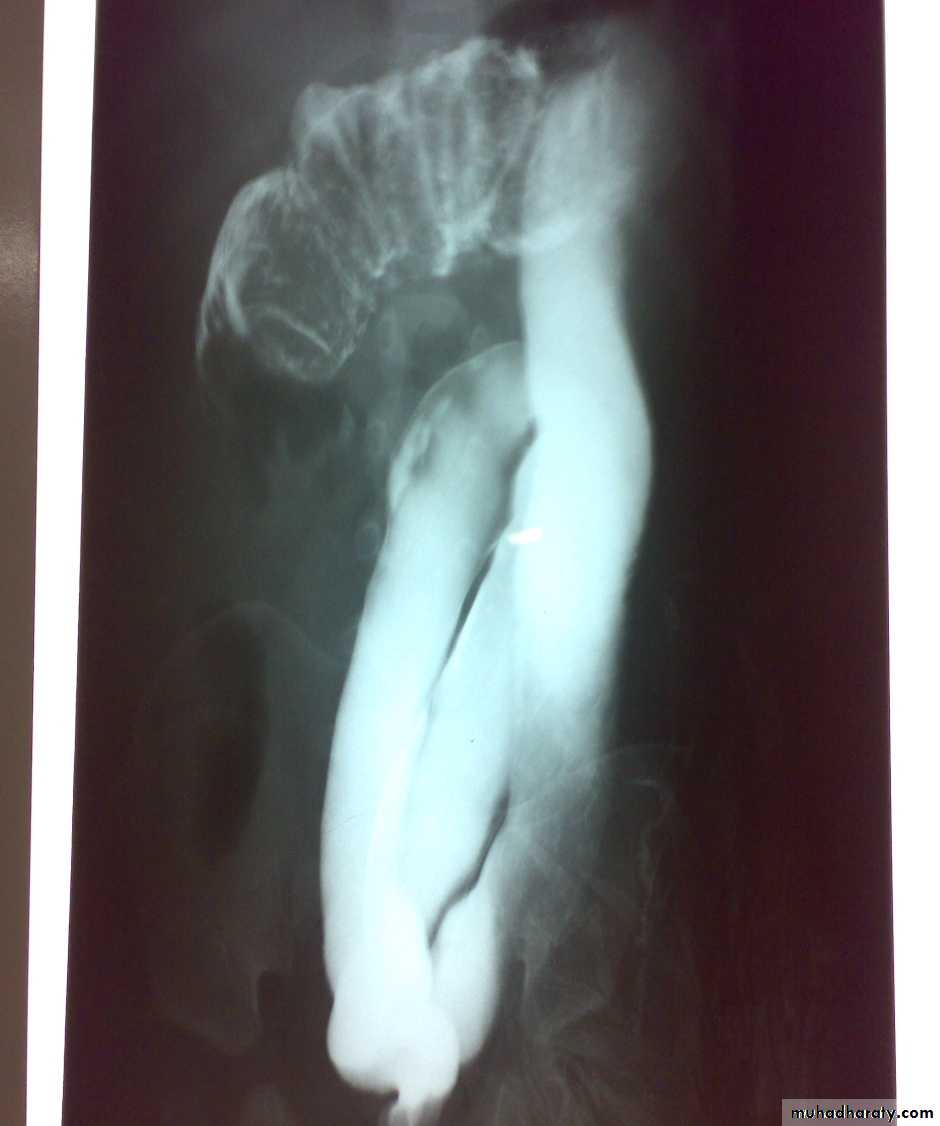

Oesophageal Atresia and Tracheo-Oesophageal Fistula,

First photo:

Diagnosis: pure atresiaDescription: radiolucent abdomen (no gases) + failure of nasogastric tube passage.

Second photo:

Diagnosis: TEF (with fistula)

Description: pass of gases to the abdomen + failure of nasogastric tube passage.

Diagnosis: TEF (atresia with fistula)

Benefits of X-ray:1- to see the failure of nasogastric tube passage.

2- to determine the type of TEF

3- to check the condition of the lung

4- diagnose the associated anomalies (aortic arch – vertebra – ribs)

5- to measure the length of the defect (1-2-3 cm or more)